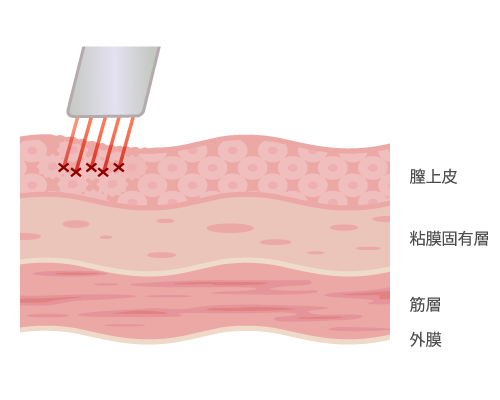

インティマレーザーは膣の奥から引き締める

インティマレーザー(Vタイトニング)は、従来のレーザーでは表面に限局されていた効果を、Fotona社独自のSMOOTH MODE(スムースモード)※技術により粘膜表面へのダメージを最小限にし、その粘膜下層に60℃~63℃の熱だまりを作ります。

この温熱効果により奥深くから膣の引締め、細胞の再構築を行うことが可能になりました。※SMOOTH MODEスムースモード:250msの超ロングパルスのエルビウムヤグレーザー